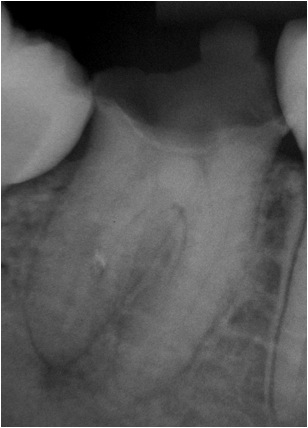

Tratamento endodôntico - dente 47 sessão única Documentação microscópica

Dente 47 - Pulpite irreversível

PQM: Limas ProTaper Universal até F5, hipoclorito de sódio 2,5% + EDTA - T

Obturação: Hibrida de Tagger